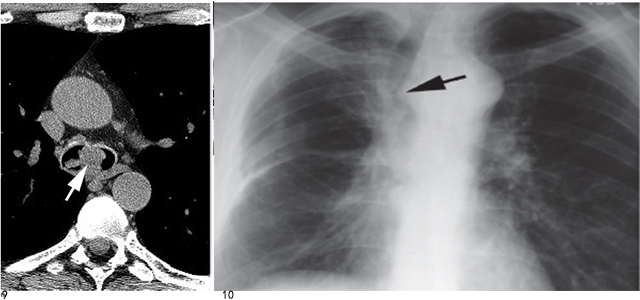

3、气管癌

鳞癌最常见于远端气管(图9),接近气管隆突,可引起一侧主支气管的阻塞;腺状囊性癌最常见于近端气管,常起源于气管的后壁或侧壁。

常见影像学表现有局灶性气管狭窄, 右侧气管旁带增厚,局灶性气管腔内病变或纵隔肿块(图10)。

图9 气管内息肉状鳞癌

在气管隆突水平可见一圆形肿块(箭头)

图10气管的鳞状细胞癌侵及纵隔

平片显示气管右侧被大的纵隔肿块(箭头) 所代替,支气管内的肿块引起气管局限性狭窄